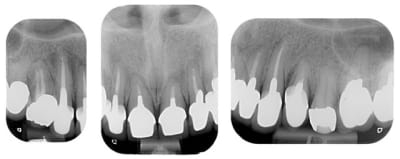

La demande concerne la réhabilitation esthétique du bloc incisif supérieur.

On ne parlera pas de bruxisme, de dvo, de gouttière et de réhabilitation globale pour diverses raisons, seule le traitement esthétique de 14 a 24 nous concerne ici et ses différentes solutions pour le traiter.

c'est dur de parler d'un cas pareil en ne voyant que 14 à 24

a part changer les couronnes, faut décider si il y a un peu de paro avant, si tu veux refaire les endos ...

A part 24 rien ne bouge, pas de douleurs, pas de problème paro, juste un problème esthétique sur ses vielles ccm.

on fait juste des nouvelles ccm ou on peut faire mieux?